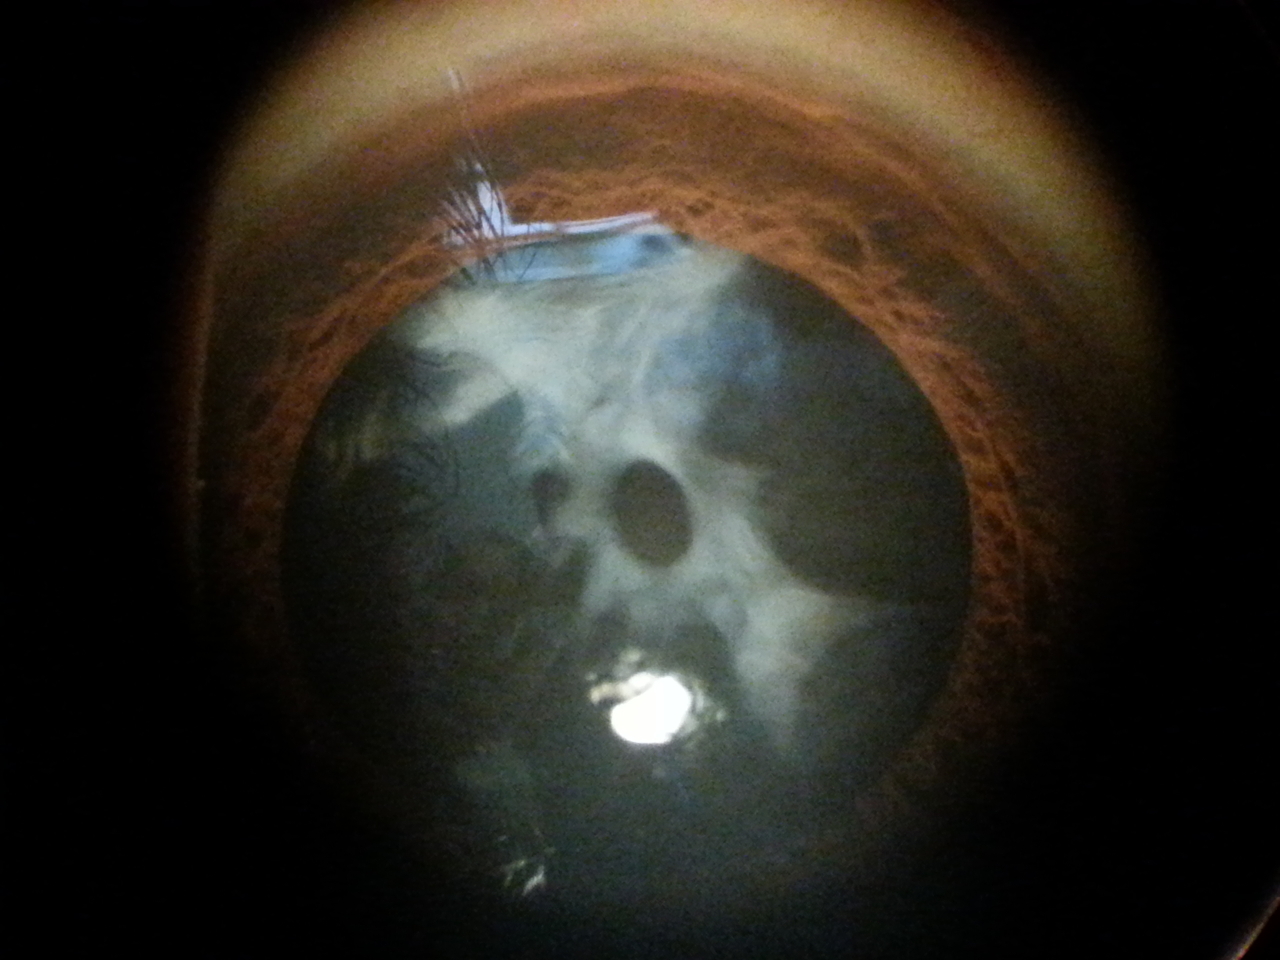

3 Fimosi e coartazione del sacco capsulare post intervento cataratta

Paziente di 44 anni ha effettuato un intervento di cataratta un anno fa, viene per una visita oculistica riferendo un forte abbassamento visivo nell'occhio operato.

L'obiettività oculistica è la seguente: visus, conta dita stentata; biomicroscopia, pseudofachia (presenza di cristallino artificiale post intervento di cataratta), fimosi e forte contrazione del sacco capsulare (vedi foto allegate); fundus, si esplora estremamente velato, non alterazioni evidenti.

Si programma intervento chirurgico di correzione di fimosi e contrazione del sacco capsulare.